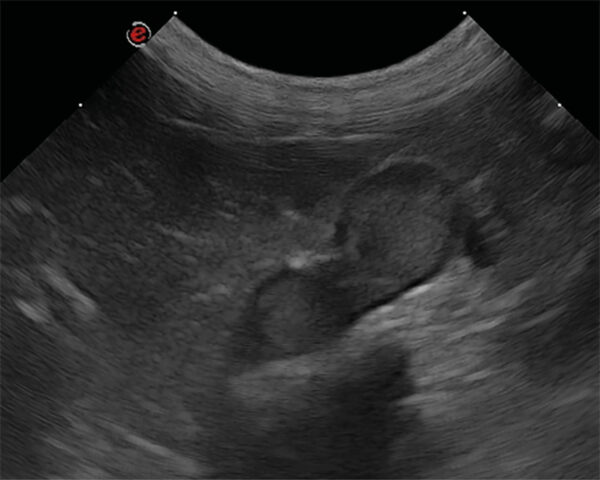

A nivel ecográfico, en perros que padecen hiperadrenocorticismo (síndrome de Cushing) generalmente se observa un aumento de tamaño de las glándulas adrenales. Este incremento es simétrico en caso de hiperadrenocorticismo de origen hipofisiario, mientras que los perros con hiperadrenocorticismo adrenal presentan una masa adrenal unilateral (imagen 2) y la glándula contralateral se identifica disminuida de tamaño o normal18.

El diagnóstico diferencial de nódulos y masas adrenales incluye hiperplasia adrenal, adenoma, adenocarcinoma, feocromocitoma y, con menor frecuencia, aunque también se han reportado: neuroblastoma, ganglioneuroma, mielolipoma, metástasis, granuloma, hematoma21. Ecográficamente no se puede diferenciar un tumor maligno de uno benigno, pero la presencia de una masa igual o superior a 2 cm de tamaño y/o la observación de invasión vascular deben considerarse criterios de malignidad22 (imágenes 3 y 4).